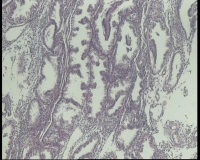

| 图片: | |

- 急!请老师看看34岁子宫内膜

| 性别 | 女 | 年龄 | 34岁 | 临床诊断 | 子宫内膜息肉? |

| 一般病史 | 末次月经:11月20日,近两个月无诱因性生活有阴道少许血性分泌物 | ||||

| 标本名称 | 宫内容物 | ||||

| 大体所见 | 膜样碎组织3.0厘米 | ||||